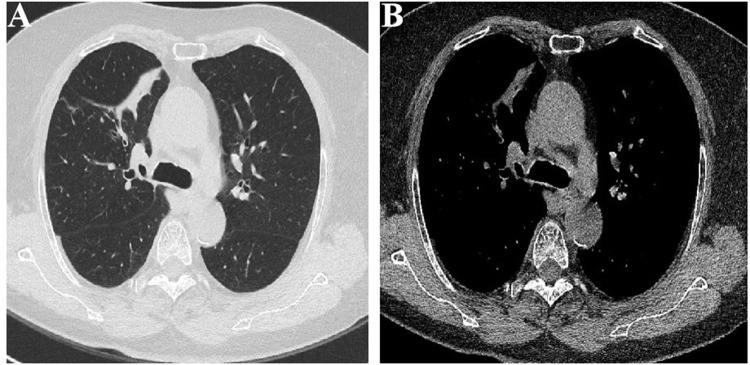

Results: Patients were predominantly middle-aged and older men. None of the tumors were detected by CT of the chest. The most common clinical symptoms were cough, sputum production, fever, hemoptysis, chest tightness and wheezing, The median symptom duration was 30 days (IQR, 7-135). The tumors were primarily located in segmental bronchi. Seventy-five percent of tumors were polypoid with wide base while 20% displayed columnar growth patterns and 5% cases had pedunculated morphology. Pathology was consistent with leiomyomas (40.0%), hamartomas (20.0%), peripheral nerve sheath tumors (22.5%) and squamous papillomas (7.5%). Rarer tumor types occupied 10.0% of all cases. Immunohistochemical analysis was consistent with pathology.

Conclusion: Primary benign tracheobronchial neoplasms are commonly small and undetectable by CT of the chest. Coupled with nonspecific symptoms this demands a high index of suspicion including in patients with coexisting conditions such as TB. Definitive diagnosis required bronchoscopy with histologic assessment.